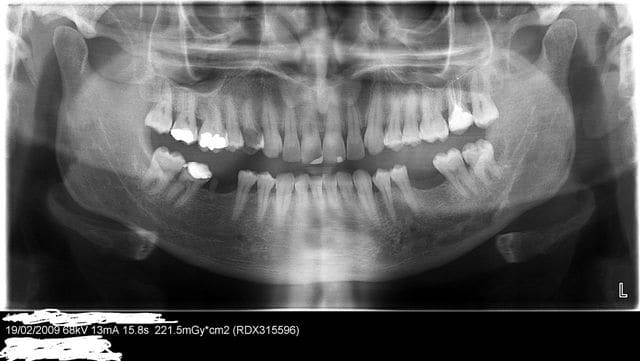

22/04/2009 à 15h24

voici sa pano

L'observation clinique et radiologique révèlait, des caries, dent à l'état de racine, du tartre, des DDS en malposition et des problemes paro.

J'ai signalé au patient ses caries et insisté aupres de lui à propos de sa 14 tres cariée, et que si elle était conservable (déterminé apres curetage de la carie)il faudrait la desinfecter et faire une couronne.

Il a ensuite insisté pour que je lui fasse un plombage sur cette dent, et conservé à tout prie sa dent.